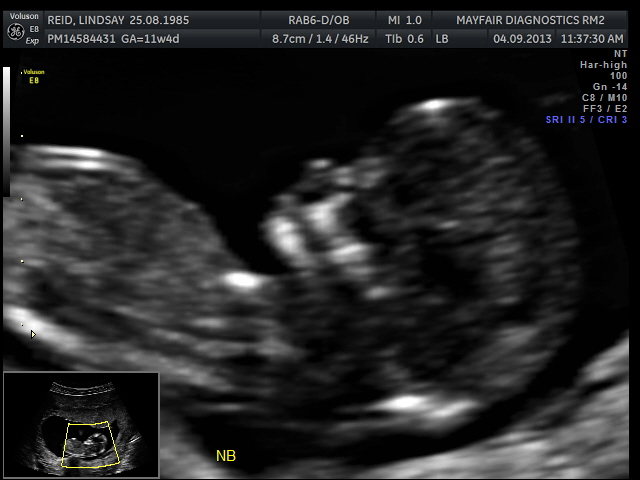

Had my 12 week scan today, I don't have any 2-d nub pics but I do have some 3-d ones! Based on the 3-d nubs and forehead/chin shape, I am guessing boy. :) Was hoping for a girl, but that's okay, lol. Heart rate was 166, baby was hyper and moving around so much!Attachment 13790Attachment 13791Attachment 13789